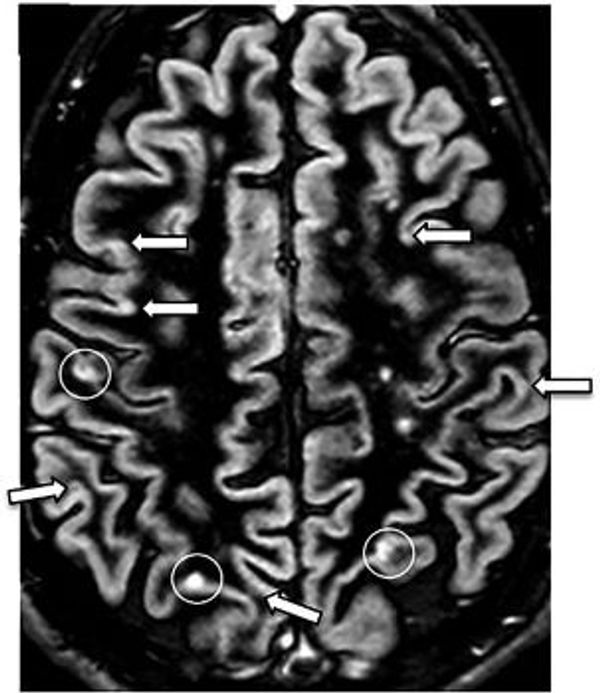

Bei Multipler Sklerose wird diese Myelinschicht angegriffen. Dies geschieht, weil das eigene Immunsystem die Nervenzellen angreift. MS wird daher auch als Autoimmunerkrankung bezeichnet. Es bilden sich Lücken in der Myelinschicht, was als Demyelinisierung bezeichnet wird. Dadurch wird die Übertragung von Signalen erschwert und schließlich manchmal sogar unmöglich. Der Körper füllt die entstandenen Löcher mit Bindegewebe auf (er kann kein neues Myelin mehr bilden), wodurch Narbengewebe entsteht, das nicht mehr isoliert. Dieses Narbengewebe ist hart, daher auch der Name der Krankheit: Multiple Sklerose bedeutet wörtlich übersetzt "mehrfache Verhärtung".